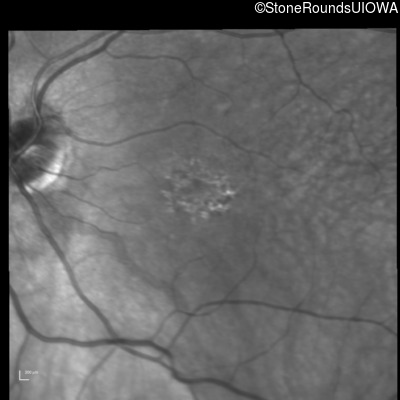

Infrared Fundus Photograph - Right - 20/100

Exemplar